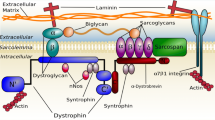

Boys with DMD experience progressive proximal to distal muscle weakness, lose ambulation in late childhood or adolescence, and die due to cardiac or respiratory failure in the 3rd or 4th decade of life [17]. Clinical deficits in arm function typically begin to appear between 9 and 14 years [4], and progress to the point where the individual no longer has meaningful use of the hands or arms. Whereas mobility aids such as wheelchairs can partially compensate for lost ambulatory function, loss of upper extremity function has a tremendous impact on quality of life, affecting the individual’s ability to eat and drink, perform personal care, and use a computer or power wheelchair.

Magnetic resonance (MR) imaging is quickly emerging as a powerful outcome measure in DMD. Quantitative MR imaging and spectroscopy (MRS) of the lower extremity muscles have proven to be sensitive to disease progression [7, 22], predict ambulatory functional ability [1], and detect the therapeutic response to corticosteroids [11]. Multiple pharmaceutical companies have started to incorporate MR biomarkers of lower extremity muscles as secondary or primary outcomes in clinical trials. Unfortunately, few studies have explored the feasibility of implementing quantitative MR (qMR) strategies to evaluate the upper extremity musculature in boys with DMD. Two groups have monitored muscle pathology in the forearm muscles of both ambulatory and non-ambulatory patients with DMD [10, 18, 20], but to our knowledge no previous MR studies have examined the proximal upper extremity muscles, such as the biceps brachii (BB) or deltoid (DEL).

This study demonstrates for the first time that it is feasible to implement quantitative MR imaging measures of muscle pathology in the proximal upper extremity musculature in patients with DMD. MR biomarkers of the proximal upper extremity muscles differentiated control and affected subjects and strongly correlated with functional endpoints. Previous studies have shown that MR biomarkers in the forearm detect disease progression in DMD [10, 18, 20], but to our knowledge, the more proximal muscles necessary for eating and personal care have not yet been examined.

Similar to the lower extremity [8], T 2 in the upper extremity muscles was elevated compared to CON, even in 7-year-old boys with DMD (the youngest boys studied), making this a potential early disease marker. Both MRI-T2 and MRS-T2 have been previously shown to decrease with steroid treatment [3], indicating that these biomarkers may be particularly suitable for use in clinical trials of anti-inflammatory compounds, including corticosteroids and steroid alternatives. MRI-T2 in the BB was also strongly correlated with functional ability, more than any other variable, indicating that BB MRI-T2 captures disease progression (likely fat infiltration) as well as being sensitive to early disease processes such as muscle damage, edema, and inflammation.